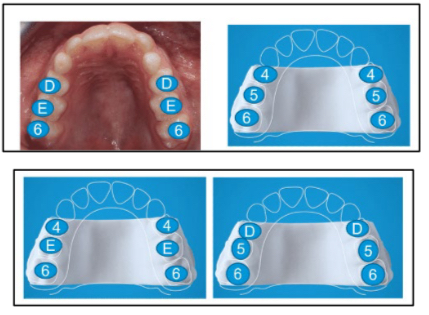

Orthodontics for kids involves more than just moving teeth. It includes dentofacial orthopedics, a term that translates to simultaneously guided dentition growth and facial bone growth. This early phase of orthodontics is the first of two phases of orthodontic care and starts when kids are well under 10 years of age. A big benefit to phase one orthodontics is that we can utilize the primary molars as appliance supports. Appliances for phase one orthodontics include palatal expanders and early clear aligners.